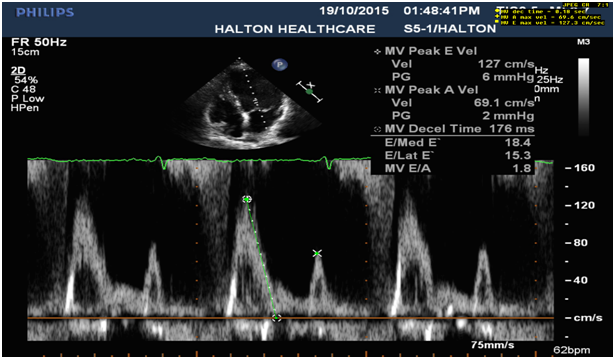

6. Systolic reverse blood flow in pulmonary vein (Figure 5) and dominant E wave in MV inflow with elevated LA pressure and high LV diastolic pressure (Figure 6).

Figure 6: E- wave dominant mitral inflow (E>1.2m/s) with signs of elevated LA and high LV diastolic pressure (L wave).